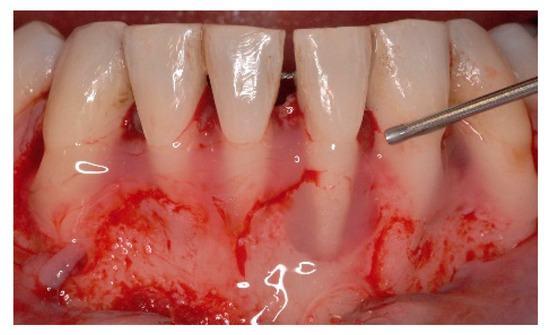

5. Materials and Methods

6. Results